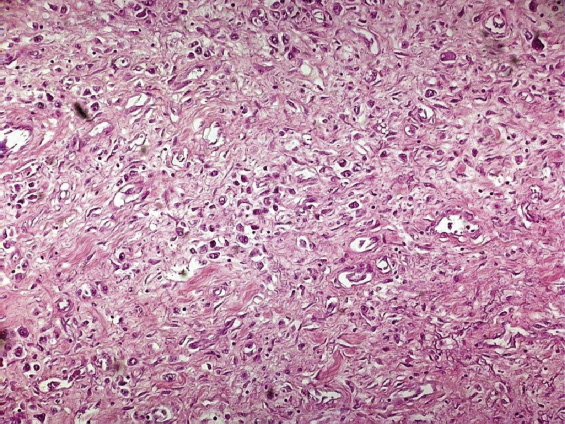

Figure 1. Microscopic examination of the abdominal mass: histology highlights a poorly differentiated neoplasia with sarcomatoid features. Further characterization of the neoplasm was not technically feasible

At microscopic examination, the abdominal mass was constituted by a poorly differentiated neoplasia with sarcomatoid features (Figure 1).

A further typization with all the available histopathological technique was not feasible at our centre, thus confirming the extremely non-differentiated features of this neoplasm.